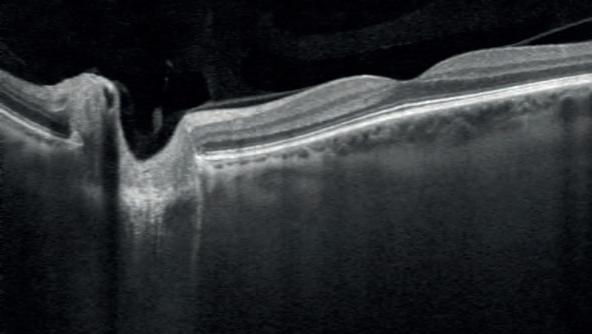

An Australian study has shown that cataract surgery using multifocal intraocular lenses (mfIOLs) can achieve good outcomes for patients and be cost-effective in a public hospital setting.

Cataract surgery is a safe and effective procedure that is performed in both the private and public sectors, and advances in lens technology now offer the possibility of multifocality.

However, mfIOLs are not readily available in the public sector, due to the complexity of patient selection and of trainee experience with them.

A study at Sydney’s Westmead Hospital showed it was possible to develop a trainee-led selection pathway that ensures the cost-effectiveness of mfIOL implantation within the government funded health system.

As part of the single-surgeon prospective cohort study, 54 eyes from 27 patients underwent cataract surgery with mfIOL implantation.

The study evaluated outcomes including the resultant visual acuity, the experience of visual disturbances, dependence on glasses and patient satisfaction.

They also performed a cost analysis.

Multifocal IOLs are not available in the public system for various reasons.Image: arren Schere/ Shutterstock.com.

most patients achieved excellent visual outcomes with mfIOLs, with high satisfaction rates reported".

“Around 85% were able to see well without glasses at a distance, 81% at intermediate distances, and 59% at near distances.”

It said the conclusion was that the additional cost of mfIOLs was comparable to the cost of glasses over time, making them a cost-effective option.

“In conclusion, the study demonstrated that the selection pathway effectively addressed challenges in choosing patients for mfIOLs in public hospitals, which can facilitate access to mfIOLs for public patients.”